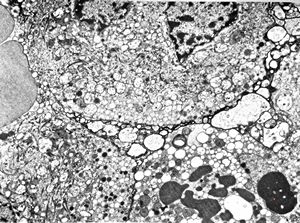

F, 45y. | carcinoid … liver metastasis